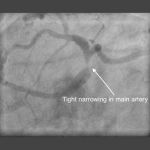

Left main stem (LMS) stenting

Left main stem…